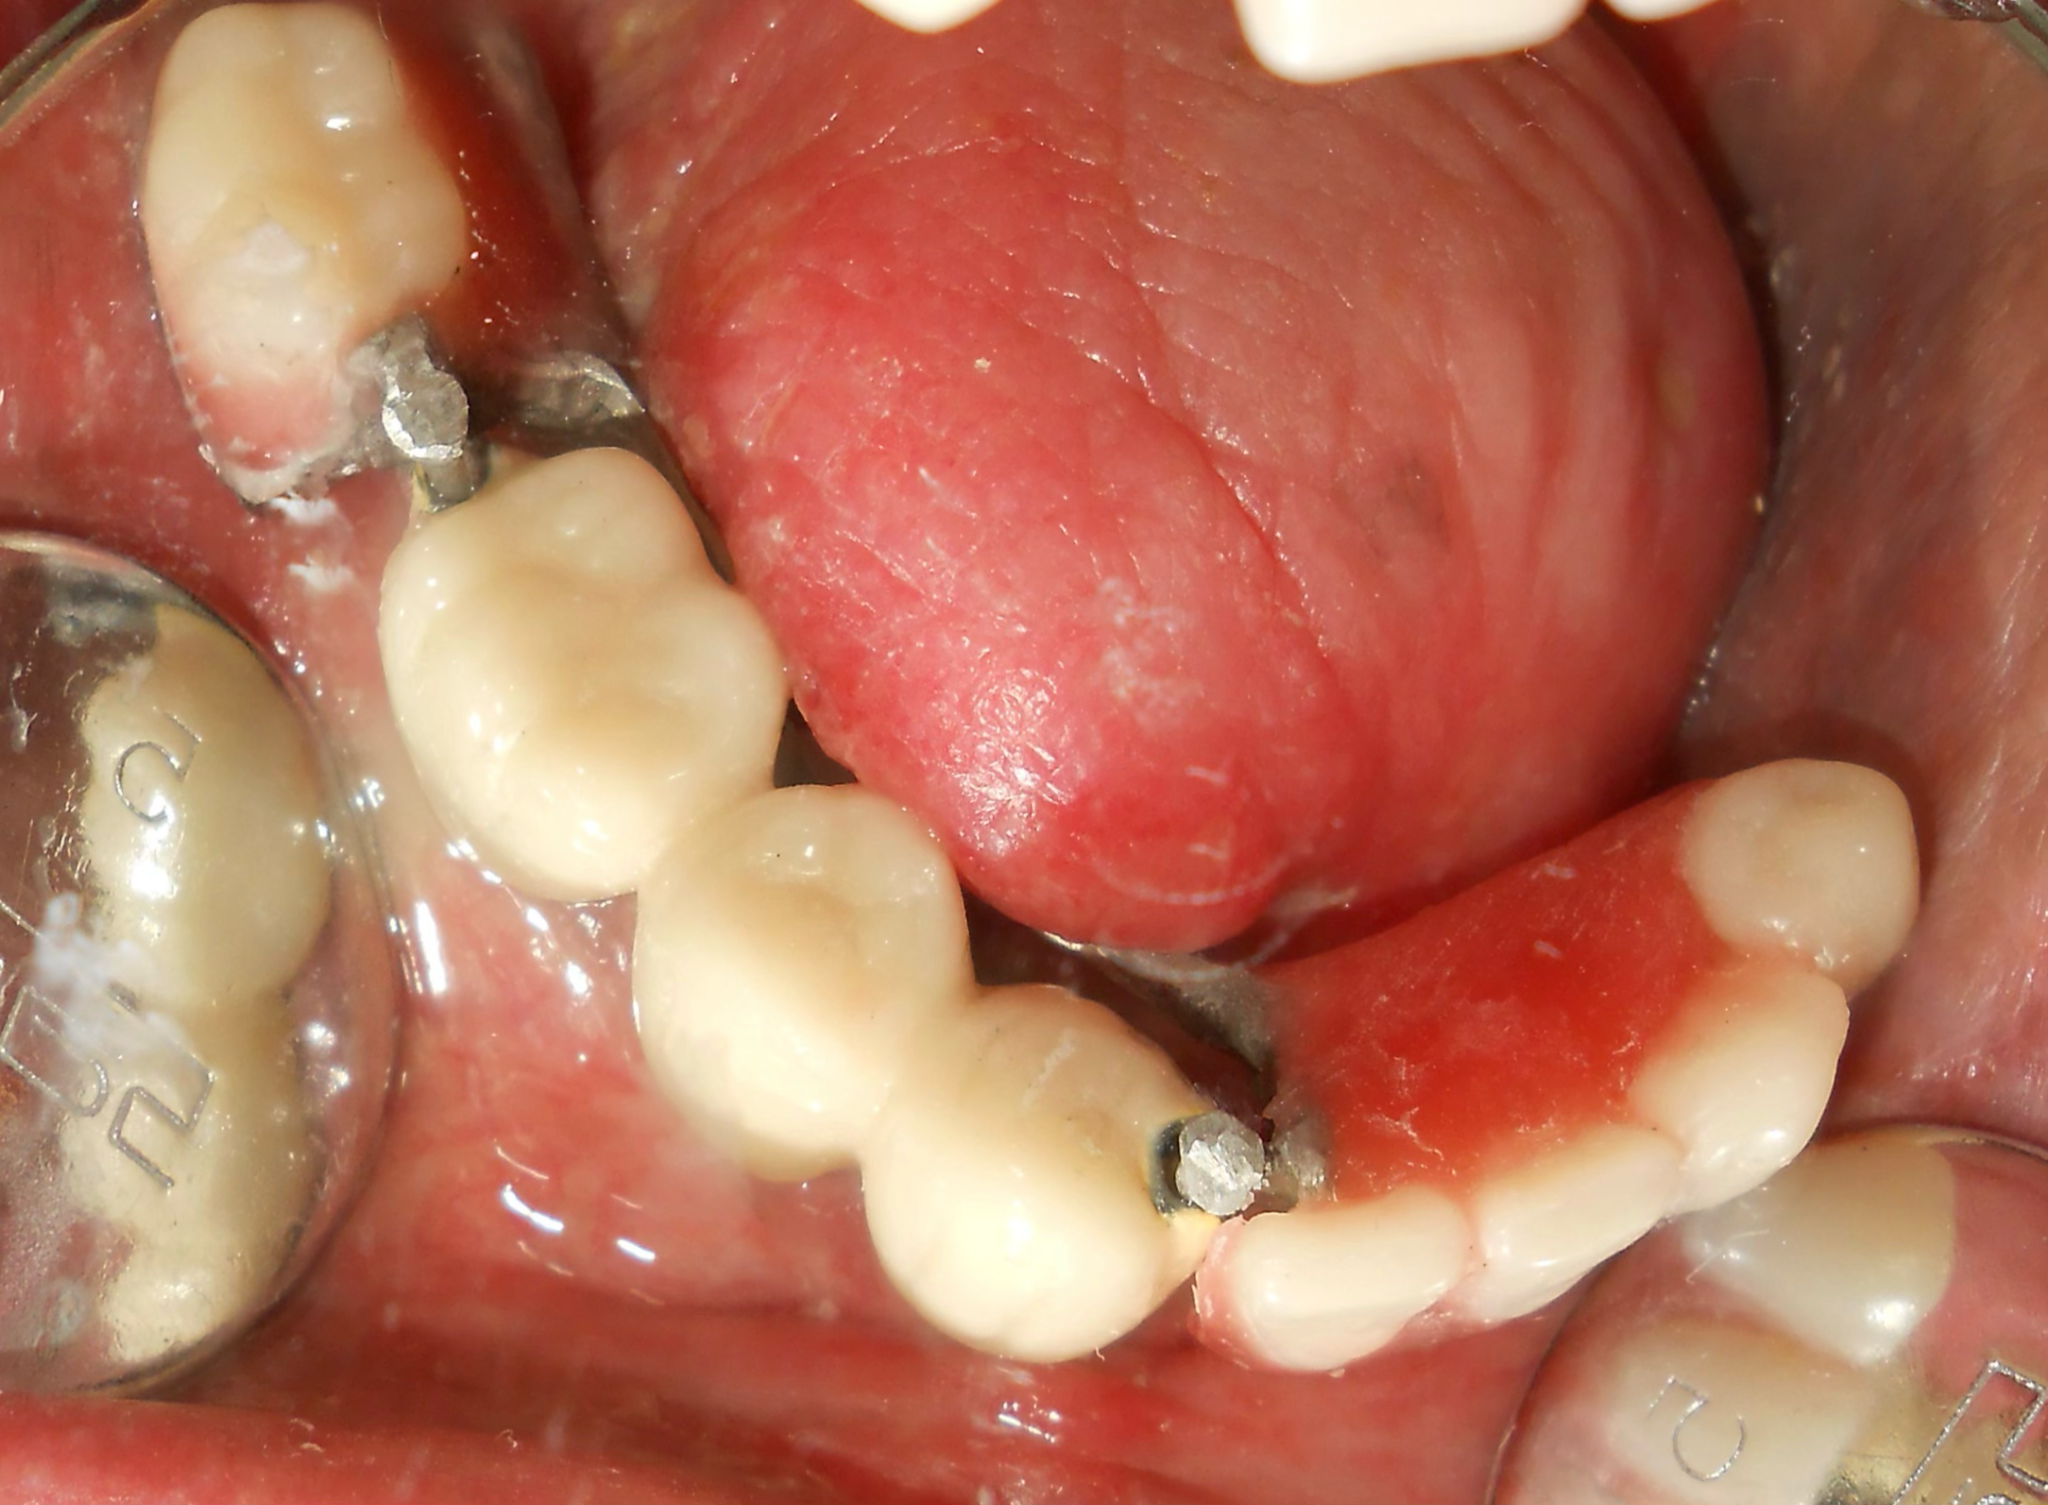

Strategic placement of 4 Dio dental implants in the regions 32, 33, 35, and 36 using advanced surgical techniques suitable for post-cancer reconstructed anatomy.

Implants were delayed loaded after 3 months with PFM crowns. Precision-attached metal removable denture was inserted for comprehensive hemimandibulectomy rehabilitation.